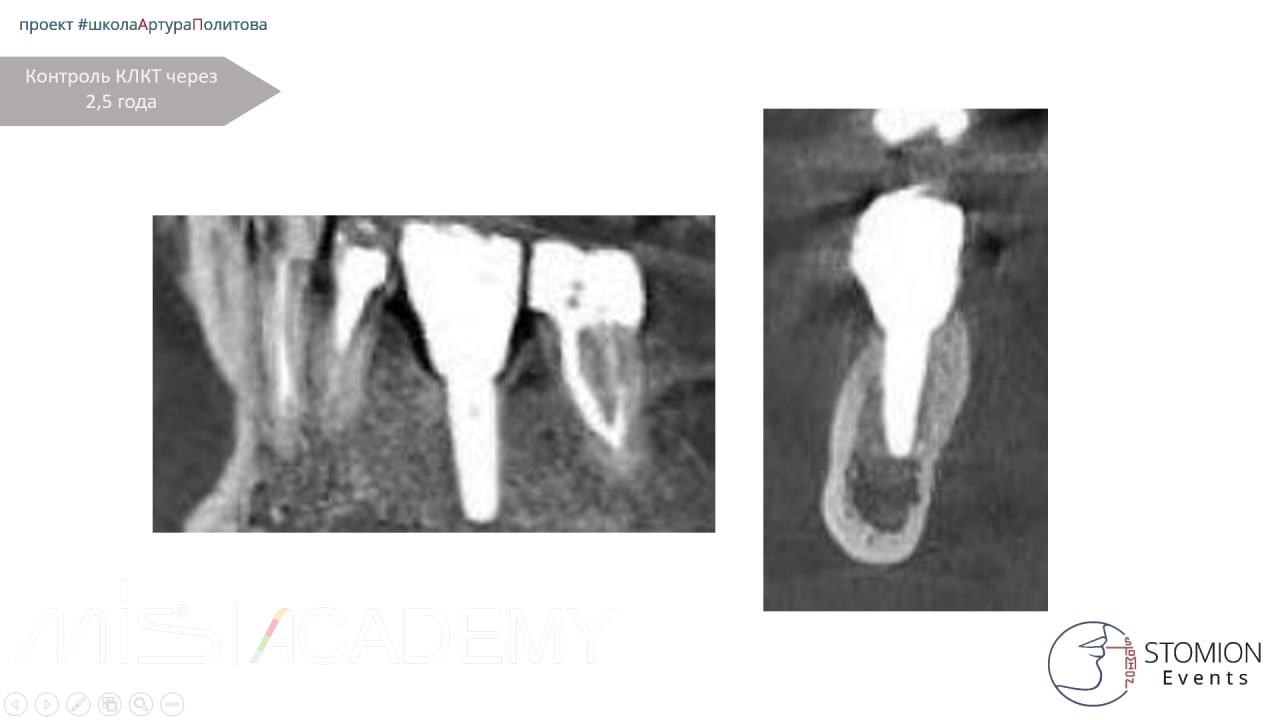

Контрольное КЛКТ через 2,5 года показало: уровень костной ткани стабилен, признаки резорбции отсутствуют, контур мягких тканей сохранён.